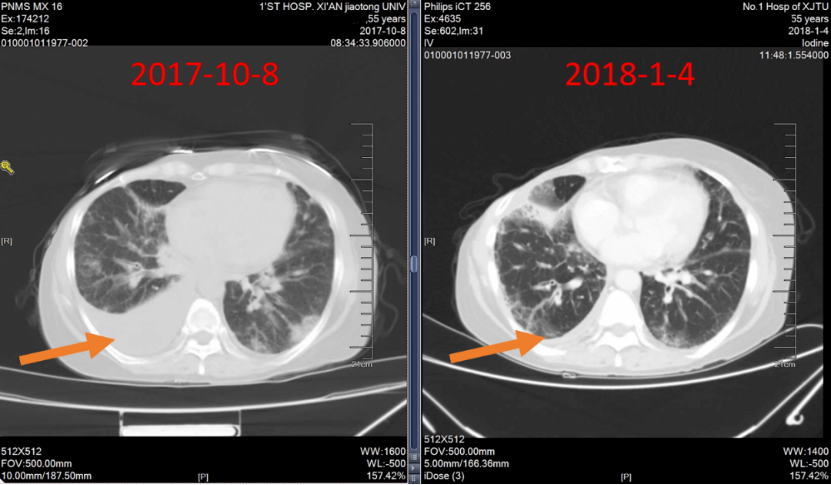

辅助检查:胸部CT(2017年10月8日)示:右乳术后,右上肺前段实变,右侧胸水(图1)。

图1:胸部CT(2017年10月8日)

2017年10月25日~2018年2月22日,给予紫杉醇脂质体周疗×12+胸腔灌注×2+伽马刀立体定向治疗,疗效评价 部分缓解(PR)。2018年3月1日~2019年12月23日,给予氟维司群进行内分泌维持治疗,定期复查,病情稳定。

一线治疗PFS达到26个月,整体疗效评价PR(图4~7)。

图4:一线治疗期间胸部CT随访

图5:一线维持治疗期间随访胸部CT